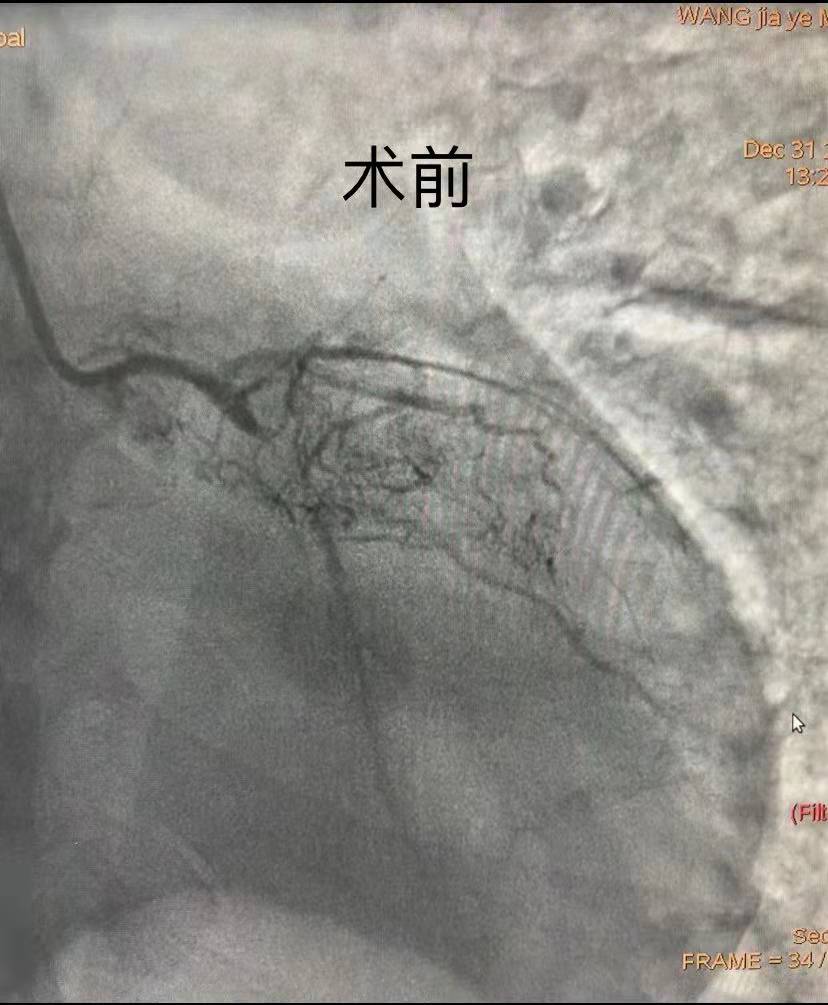

時(shí)間就是生命,時(shí)間就是心肌。在取得患者及家屬的理解及配合后,副院長汪念東、副主任徐先進(jìn)及主任助理農(nóng)彥林帶領(lǐng)心血管內(nèi)科介入團(tuán)隊(duì)制定嚴(yán)密的救治方案及應(yīng)急預(yù)案,為患者施行緊急冠狀動(dòng)脈造影,證實(shí)多支血管彌漫性病變、LAD(冠狀動(dòng)脈前降支)慢性閉塞、LCX(冠狀動(dòng)脈左回旋支)近端次全閉塞、RCA(右冠狀動(dòng)脈)近端嚴(yán)重狹窄達(dá)90%。因患者血流動(dòng)力學(xué)極其不穩(wěn)定,用大劑量血管活性藥物維持基礎(chǔ)血壓的效果并不理想,團(tuán)隊(duì)為患者應(yīng)用IABP泵,完成術(shù)前生命支持系統(tǒng)。

團(tuán)隊(duì)綜合考慮后判斷,LCX是此次心肌梗死的“元兇”。開通病變部位的機(jī)會(huì)只有一次,必須做到“快、準(zhǔn)、狠”。汪院長團(tuán)隊(duì)經(jīng)驗(yàn)豐富,技術(shù)嫻熟,導(dǎo)絲小心通過,球囊充分?jǐn)U張,最后在病變部位植入支架,所有操作一氣呵成。復(fù)查造影顯示,病變部位狹窄小于10%,手術(shù)獲得成功。